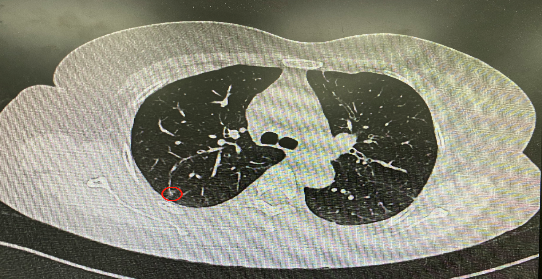

今年54歲的李女士(化名)7月初突然出現(xiàn)右上部腹痛,起初并未在意,以為稍作休息就會好轉(zhuǎn),但疼痛卻并未消退,持續(xù)了一個星期。李女士實在難以忍受,才在家人陪伴下來到西安國際醫(yī)學中心醫(yī)院就診。胸外科二病區(qū)崔凱主任接診患者后,詳細詢問病情并查閱檢查資料,經(jīng)胸部HRCT檢查,結(jié)果提示:右肺上葉后段混合密度結(jié)節(jié)影,考慮原位癌可能,即將患者收入胸腔外科二病區(qū)住院治療。

經(jīng)與患者家屬溝通,崔凱主任決定行外科手術(shù)治療。為達到精準切除,術(shù)前需進行肺小結(jié)節(jié)切除前定位。由于結(jié)節(jié)位于右肺上葉后段,傳統(tǒng)經(jīng)胸外穿刺術(shù)無法抵達病灶。崔凱主任與呼吸內(nèi)科一病區(qū)歐陽海峰主任討論后,決定擬行LungPro全肺診療導(dǎo)航下染色定位。即術(shù)前通過Lung Pro導(dǎo)航規(guī)劃染色位置,經(jīng)Lung Pro實時引導(dǎo)支氣管鏡抵達既定位置,注入亞甲藍染色劑標記結(jié)節(jié)位置。

使用術(shù)前規(guī)劃系統(tǒng)重建全肺3D模型,并于外科醫(yī)生討論染色位置,最終確定標記染色點—右肺上葉后段b亞段(RB2b)。術(shù)中使用P290(4.9mm外徑)標準支氣管鏡,根據(jù)導(dǎo)航術(shù)前規(guī)劃路徑,Lung Pro實時導(dǎo)航下,GS鞘管進入RB2b遠端官腔外病灶并注射亞甲藍染色劑。

一切準備就緒,7月15日,崔凱主任團隊聯(lián)合歐陽海峰主任團隊為患者行單孔胸腔鏡下右肺上葉后段切除術(shù),手術(shù)用時128分鐘順利完成。進入胸腔后,亞甲藍染色部位明顯,患者發(fā)生癌變的右肺上葉后段被成功切除。術(shù)后標本根據(jù)染色部位迅速找到結(jié)節(jié),剖開位置兼染色位置和病灶完全符合,行術(shù)中冰凍后快速送病理檢查。經(jīng)術(shù)后病理檢查,明確診斷為(右肺上葉)原位腺癌。